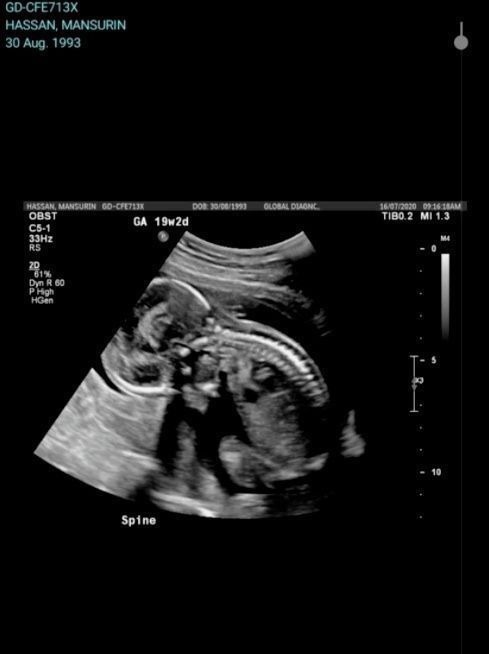

这是一起令人痛心且震惊的医疗事故,澳洲著名私立医院St John of God Bunbury Hospital因一个疏忽,导致一位澳洲孕妇肚子里整整十个月的宝宝胎死腹中....而孕妇自己也差点永远醒不过来。事件的主人公Sarah Hassan和丈夫Sunny Alam在两年前移民到了澳洲,在移民澳洲不久后,Sarah就怀孕了。他们全家都满怀期待着孩子的出生,但谁也没想到,不幸会降临到他们身上。

2020年12月9日,Sarah在预产期的第二天开始宫缩,在丈夫的陪同下,Sarah住进了St John of God Bunbury Hospital进行检查。在医院检查过后,他们被告知孩子出生还有一段时间,因此他们可以选择是留在医院过夜还是回家。为了稳妥,他们选择留在医院。但当时她非常紧张,医生见状就建议她用吗啡来帮助放松。最开始,Sarah是不打算用药物的,想着忍忍就过去了。但到了晚上11点左右,越来越频繁的宫缩,让Sarah实在坚持不住。于是她就同意了医生的建议,接受了药物注射。这一针下去,Sarah直接就昏迷了。

丈夫Alam对媒体表示:“早上,当护士来看我妻子时,Sarah没有了脉搏,随即立即按响了急救铃。二三十名医生和护士立即冲进病房,试图用心肺复苏挽救她的生命,因为她心脏呼吸停止了。”在意识到事态的严重性后,医院当时就赶紧对Sarah进行了剖腹产。但为时已晚,孩子已经在因缺氧死亡了!Alam悲痛欲绝地说:“他仍有体温我没法相信他已经死了,不,我认为他还活着,我不敢相信……”但就在他悲痛万分的时候,医生还告诉他,他的妻子因过量吗啡,依旧在深度昏迷中!

由于Sarah长时间缺氧,她的心脏和肺不能正常工作,而且有可能大脑受损。随后,Sarah被紧急送到数百公里外的Fiona Stanley Hospital继续进行急救,4天后,她终于脱离了生命危险。而当Hassan终于从昏迷中醒来后,听到的却是孩子离去的噩耗。十月怀胎将为人母的美好愿望落空,这种突如其来的打击究竟有多大,根本不是我们能想象得到的...

孩子的去世都是因为那一剂针药,据悉,当时医院给她注射的吗啡剂量,居然是处方剂量的10倍!这么大剂量的吗啡,别说是她腹中的孩子,就是Sarah本人也是侥幸活命!St John Bunbury医院在一份声明中说,可能发生了“严重的临床错误”,根据最新信息,医学研究人员认为这是人为错误造成的,属于医疗事故。